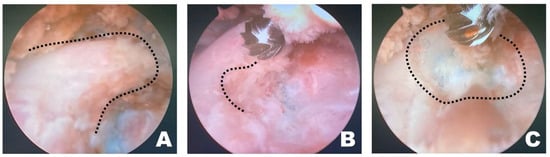

Once a clear view of the working space for accessory process osteotomy was established (Figure 4A), burr osteotomy was performed to ensure that it was securely seated on the wider surface of the caudal aspect of the accessory process to prevent slipping (Figure 4B). Thus, the osteotomy site served as the surgical window (Figure 4C). If nerve exposure and potential nerve damage increased owing to insufficient burr osteotomy, an additional osteotomy was performed with a shaver. If precise soft tissue trimming was performed, FDADM-MB could be observed through the transforaminal site without osteotomy of the accessory process, alongside the epidural fat (Figure 4).

Figure 4.

Osteotomy of the accessory process in the endoscopic view toward the left. (A) The dashed line indicates the T12 accessory process. Clear and distinct observation was possible; the fluorescently dyed artificial disc material with methylene blue was observed at this time. (B) The dashed line marked the initiation point of osteotomy. Osteotomy was performed by securely placing the burr on the widest surface of the caudal aspect of the accessory process. (C) The dashed line indicates the surgical window. Additional osteotomy was extended along the dashed line.

Upon overserving the FDADM-MB, after removing intervertebral foraminal and intraforaminal ligaments, it was removed using a microngeur (Rita, Mulheim, Germany) (Figure 5) [55]. FDADM-MB on the ventral aspect of the spinal cord, which could not be removed with the microngeur, was extracted using a microprobe (Rita, Mulheim, Germany). After maximal removal, the probe was inserted under the spinal cord, slightly retracted dorsally, and checked for the remaining FDADM-MBs.

Figure 5.

Identification and removal of the fluorescently dyed artificial disc material with methylene blue (FDADM-MB) in the endoscopic view toward the left. (A) The FDADM-MB was clearly visible in blue through the completed surgical window after removing various intervertebral foraminal and intraforaminal ligaments using forceps. (B) Repeated use of the micro-ronguer to remove all removable disc material. A clear observation of the spinal cord and nerve root was achieved, and the residual FDADM-MB remained after removal.